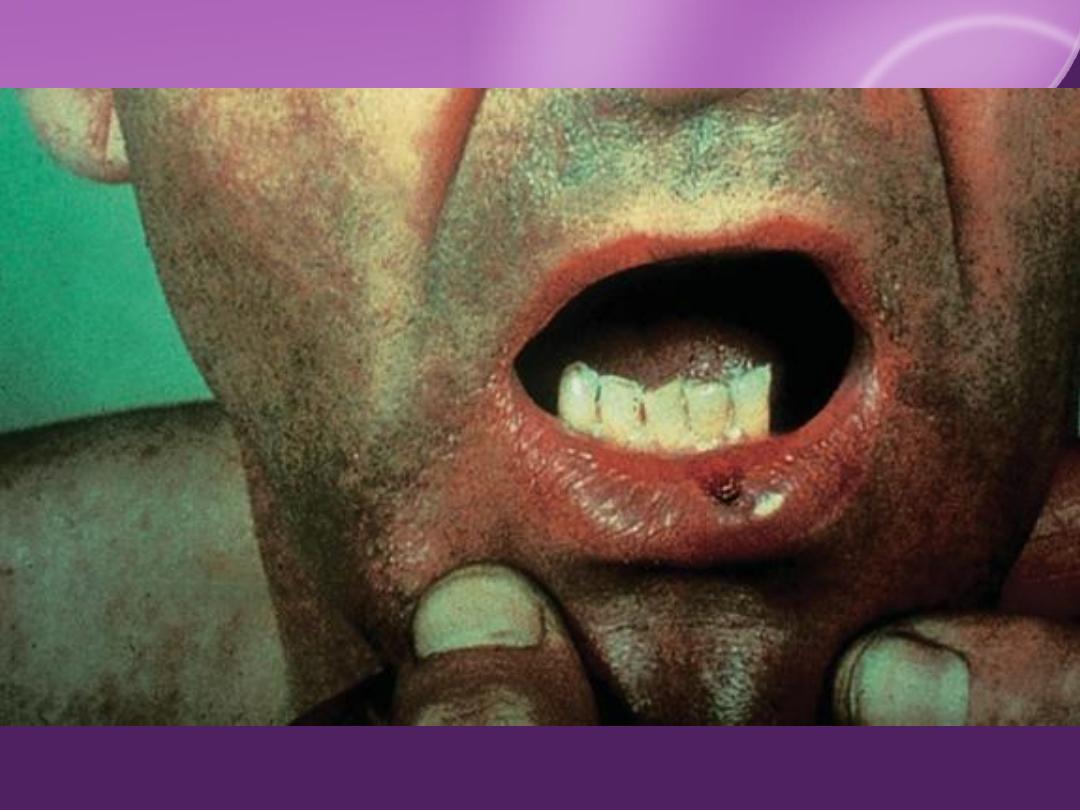

Secondary Syphilis:

Cutaneous Findings:

Flulike symptom and generalized painless

LN in 50%

"Moth eaten" alopecia

MM involvement

Extremely infectious

Genital (codylomata lata)

Oral, pharyngeal, laryngeal.

Condylomata lata

Oral lesions